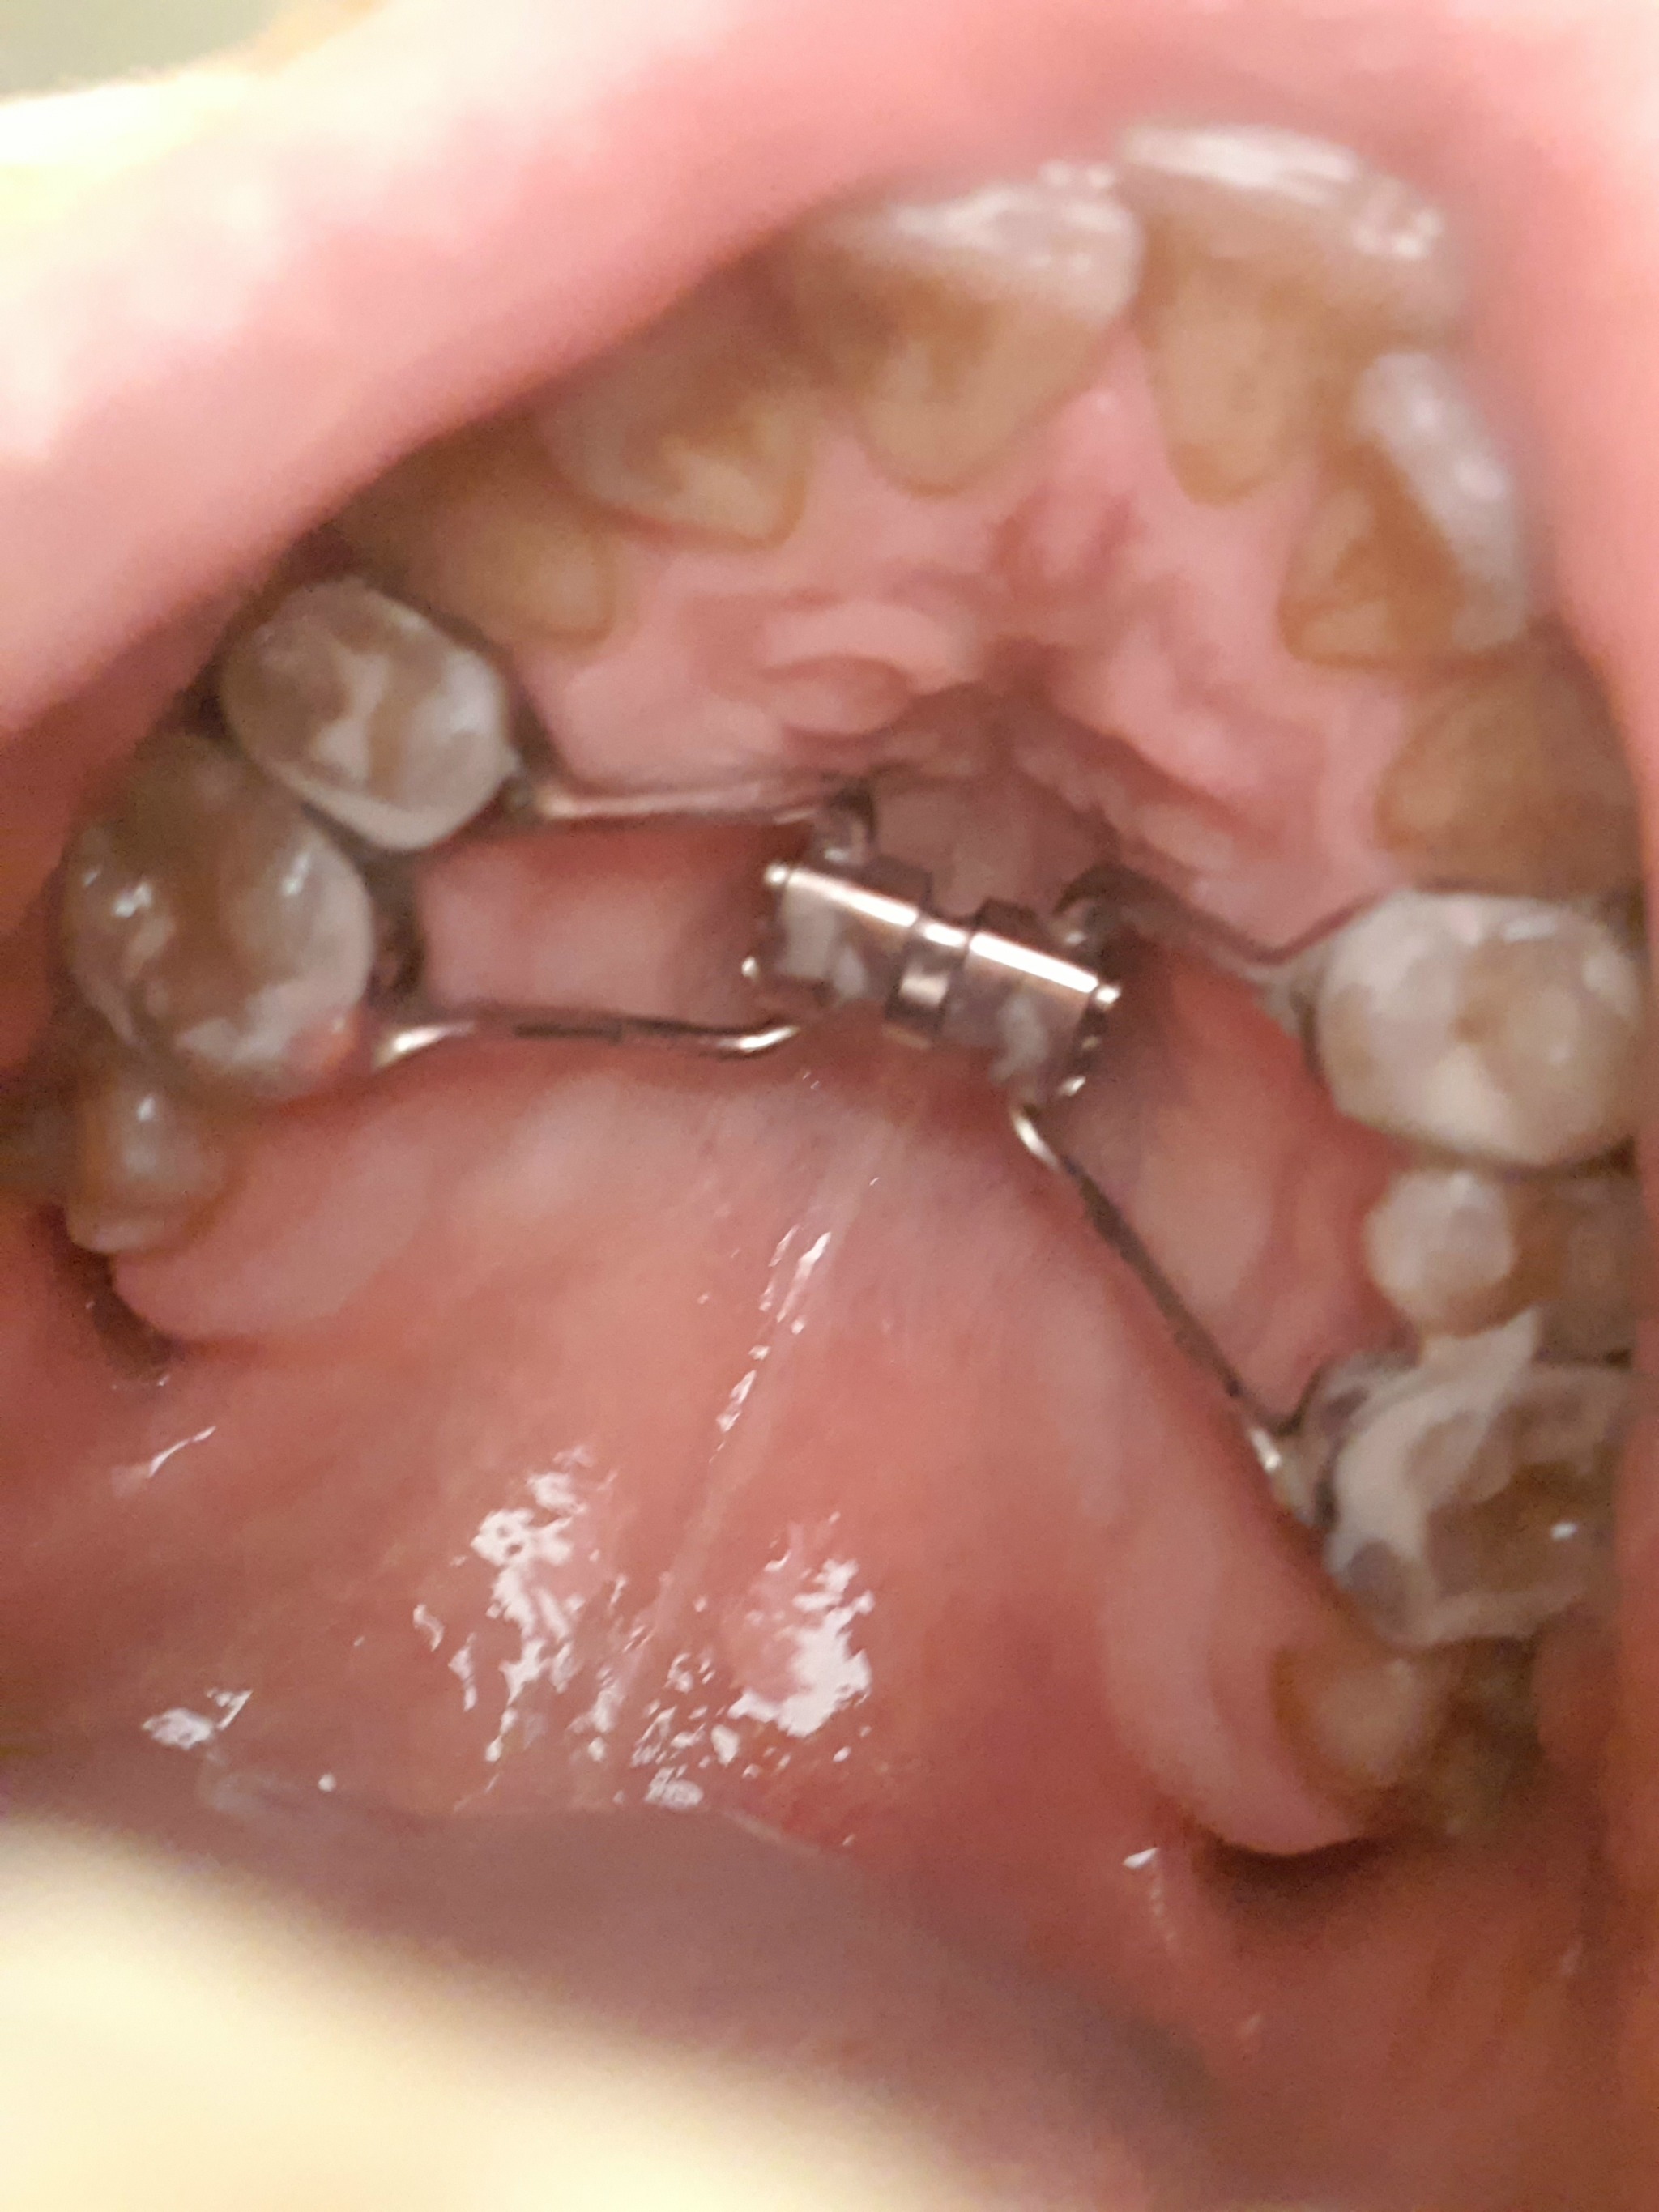

Итак, братцы, дело пошло...Дистрактор установленный кручу каждый день по 1 мм, начала появляться щель между передними зубами, это не больно, но ощущение что внутри черепа что-то давит в стороны. По обещаниям ортодонта скоро там будет около 1 см.

Прикладываю обещанные фотки: как было и промежуточный эффект. Завтра снятие швов. Полет нормальный